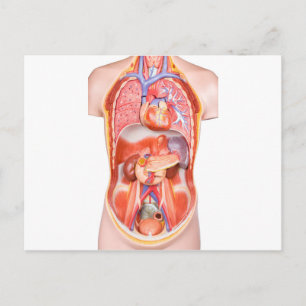

Human Yta Anatomy Relation till organ Poster

Pris258,00 kr

Human Yta Anatomy Relation till organ Poster

Pris258,00 kr